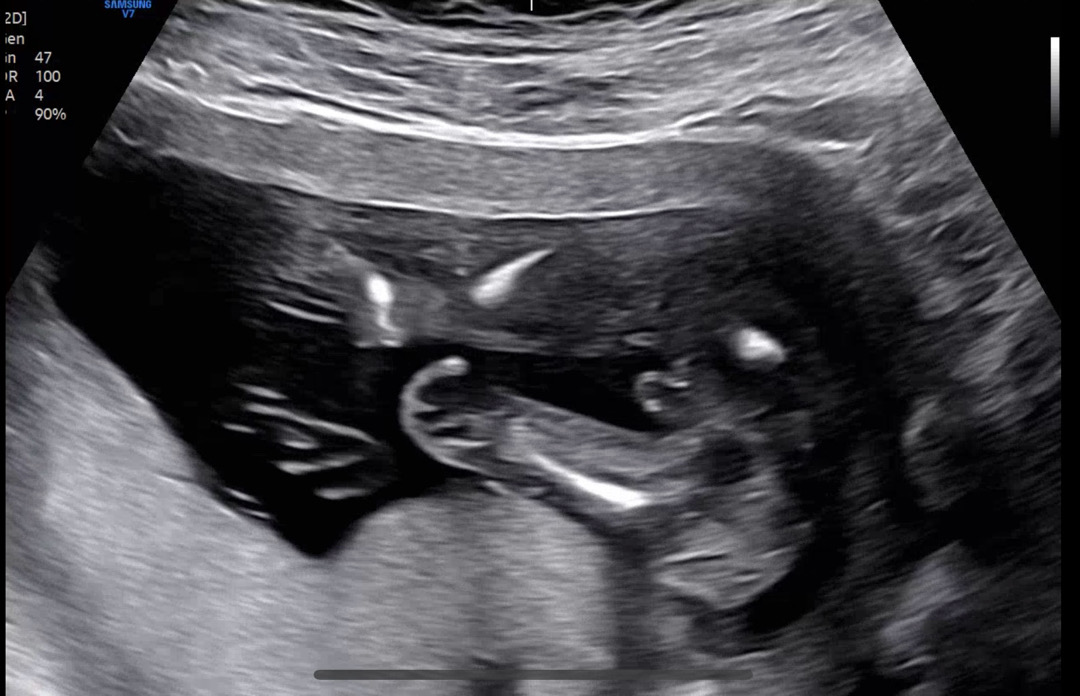

16주 촘파사진!😁

아니…우리 쌤이 뭐가 보인다는데 이거 진짜 보이는거 맞나여…?ㅋㅋㅋ 16주0일인데 20주에 반전이 있을까용..?😅ㅎㅎ

초음파 사진상으론 아들이실것 같아요 미리 축하드려요^^ㅎㅎㅎ남자아이들이 어릴땐 엄마 껌딱지하다가 커서는 든든한 보디가드가 되어준대요

16주 딸은 반전 있어두 아들은 그전이여도 거의 반전없어용

16주에 보인거면 반전 거의없대유!!